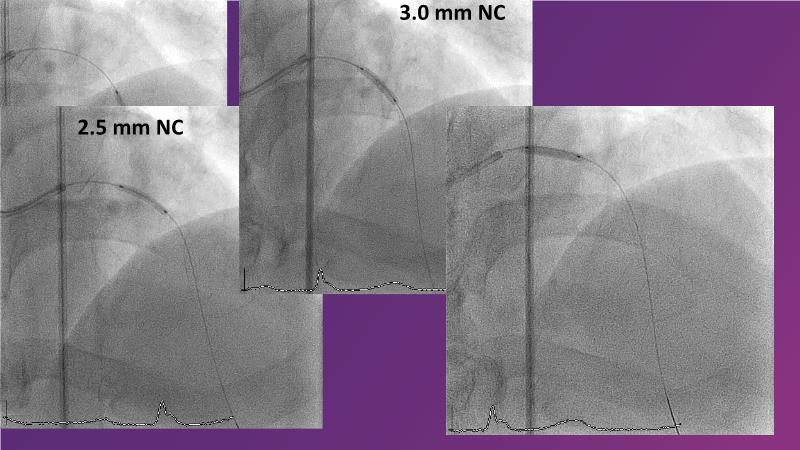

Watch this session to gain case-based insights on using DCBs in complex settings. Learn valuable tips and tricks for optimal DCB application, including the best timing and situations for their use. Discover how to effectively implement a hybrid strategy that combines DES and DCB when needed.

- To get a case based experience on how to use a DCB in complex settings

- To learn about tips and tricks on how and when to use a DCB: the ideal time and situation of DCB application in various complexities

- To utilise the hybrid strategy approach Combining DES and DCB when the situation demands